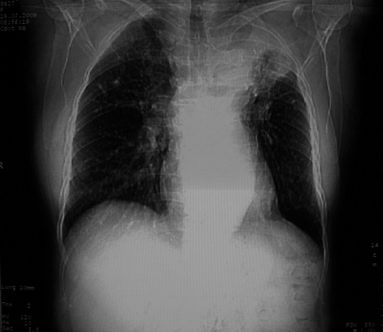

以下是引用李衡钧在2008-7-24 14:24:00的发言:[br]左侧胸廓变小,左肺上叶见大面积致密阴影,其内有空洞及不规则钙化。上纵隔略向左移位,上肺胸膜增厚。左肺门及纵隔淋巴结增大。右肺见散在的致密结节影。[br]印象:继发性肺结核。